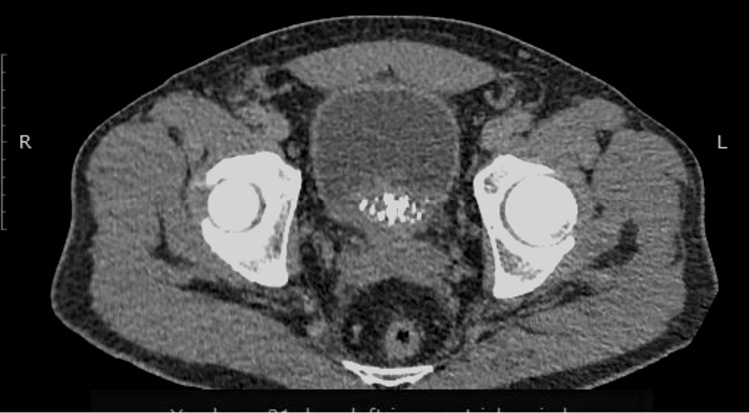

С 08.2022 по 22.12.2022 проведено 6 курсов лекарственного лечения по схеме карбоплатин + иринотекан. По результатам контрольного обследования от 01.2023: отрицательная динамика в виде увеличения размера очагов в костях скелета: в левой подвздошной кости до 29×25 мм (ранее до 25×23 мм) и 38×26 мм (ранее до 33×25 мм), в крыле подвздошной кости до 56×19 мм (ранее 27×22 мм), в боковой массе крестца слева до 28×23 мм (ранее 27×22 мм) и появления новых мелких очагов в бедренных костях до 5 мм и в телах LII–IV позвонков диаметром до 3 мм; билобарного очагового поражения печени: в S2 – до 20×23 см, на границе S2|3 – до 13×15 см, в S6 – 8×11 мм (рис. 9, 10).

Рис. 9. КТ органов брюшной полости от 02.11.2022 в сравнении с КТ от 11.01.22. КТ-картина билобарного очагового поражения печени: в S2 – до 20×23 см, на границе S2|3 – до 13×15 см, в S6 – 8×11 мм.

Fig. 9. Abdominal CT scan dated 02.11.2022 in comparison with CT scan dated 11.01.22. Bilobar focal lesions of the liver: in S2 – up to 20×23 cm, at the border of S2|3 – up to 13×15 cm, in S6 – 8×11 mm.

Рис. 10. КТ органов брюшной полости от 02.11.2022 в сравнении с КТ от 11.01.2022. КТ-картина билобарного очагового поражения печени: в S2 – до 20×23 см, на границе S2|3 – до 13×15 см, в S6 – 8×11 мм.

Fig. 10. Abdominal CT scan dated 02.11.2022 in comparison with CT scan dated 11.01.2022. Bilobar focal lesions of the liver: in S2 – up to 20×23 cm, at the border of S2|3 – up to 13×15 cm, in S6 – 8×11 mm.